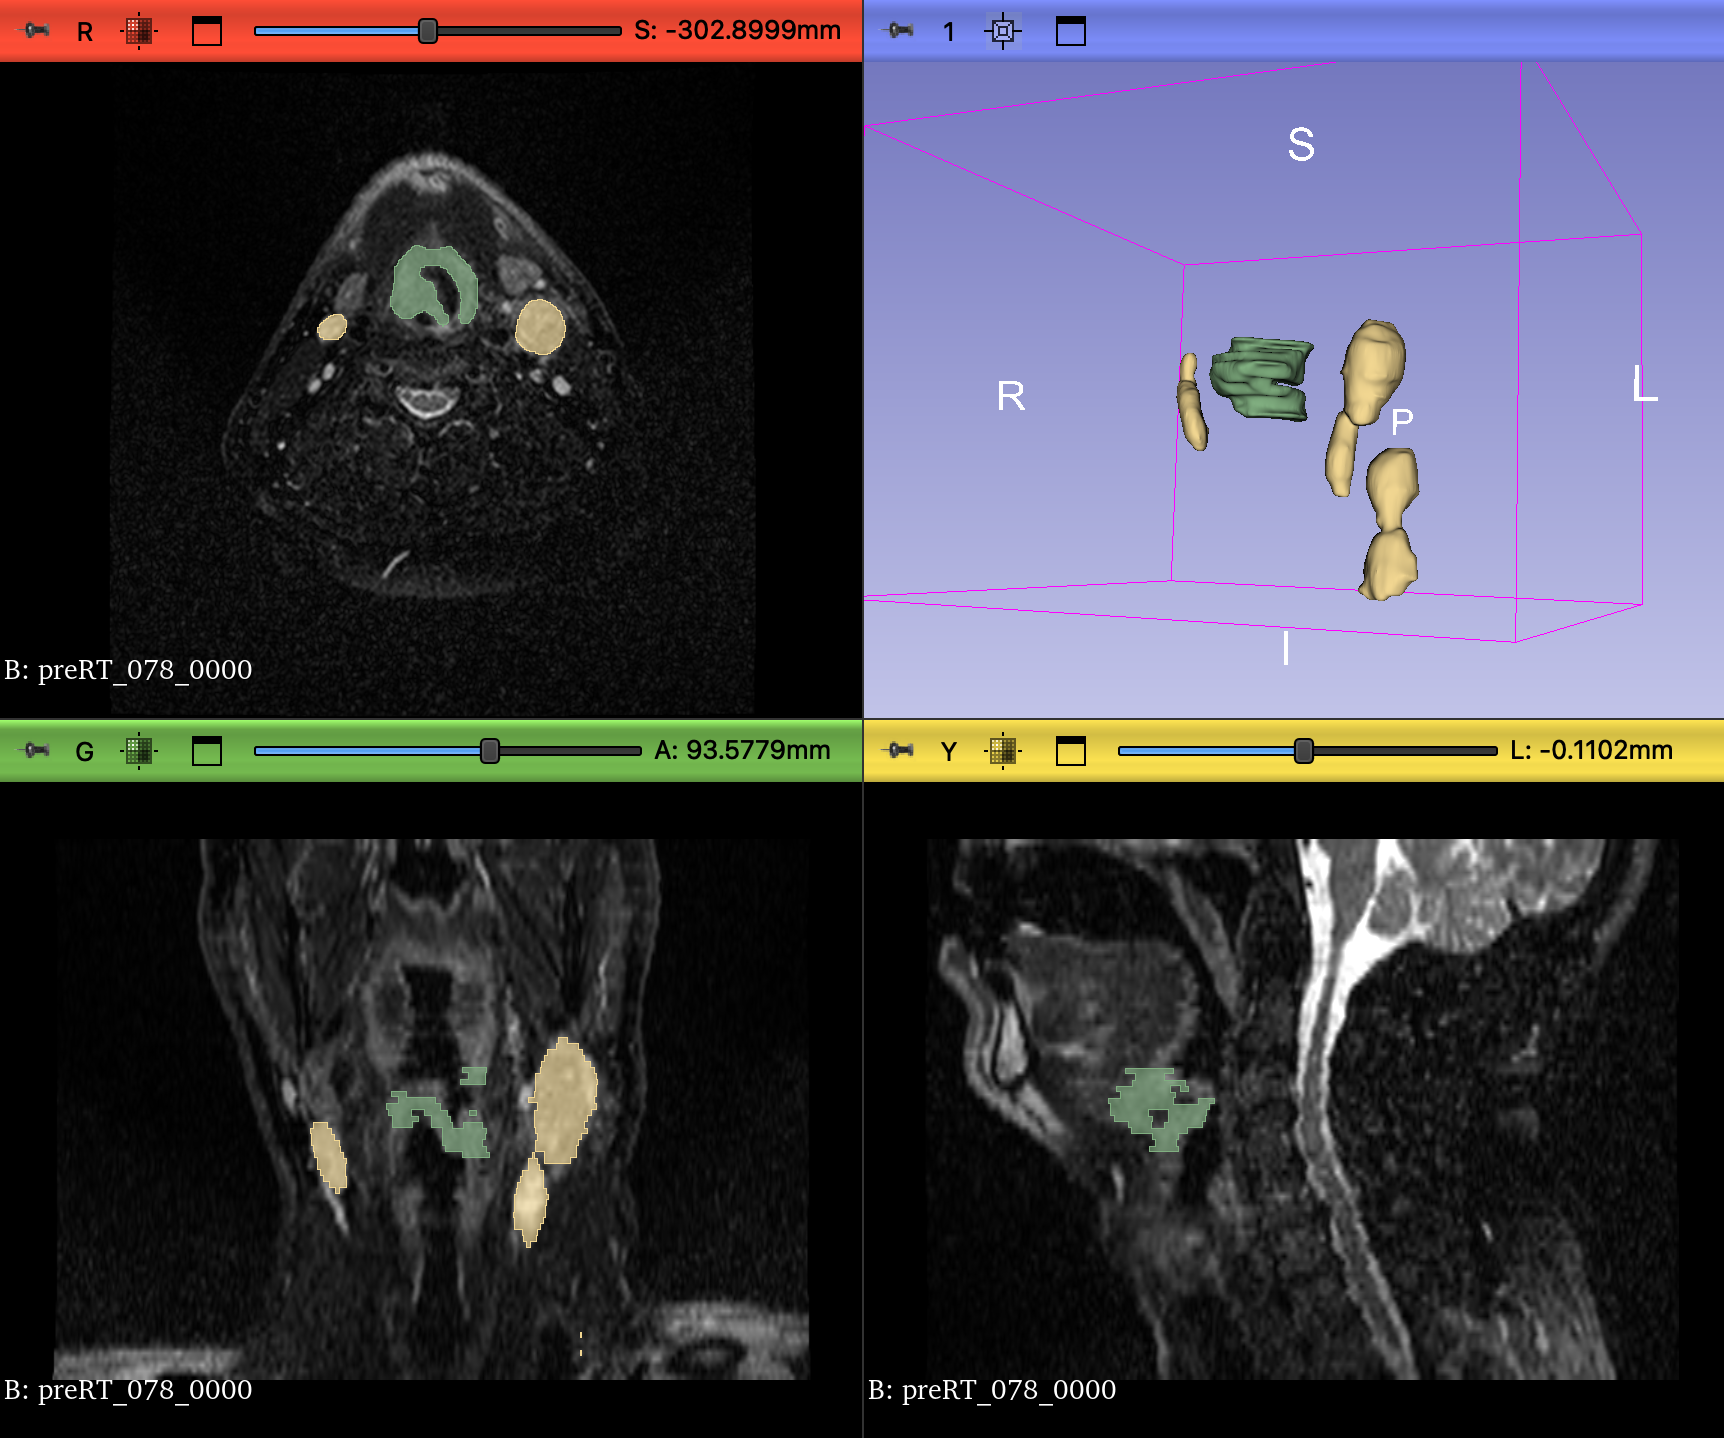

For Task 2, the input consisted of a multi-channel format combining mid-RT, pre-RT registered images, and the corresponding pre-RT registered segmentation. All 150 cases were used to train nnUNet, but we encountered issues while training MedNeXt. To resolve these issues, cases with zero ground truth for either label 1, label 2, or both were discarded, leaving 115 samples after removing 35 cases. An example of a pre-RT image with its segmentation is shown in Figure 1. All the visualizations in this paper were created using 3D Slicer [13].

Figure 1: A sample pre-RT image (Case 78) with its corresponding segmentation. The green label represents GTVp (label=1), while the yellow label represents GTVn (label=2). The images show axial, coronal, and sagittal views, along with a 3D rendering of the segmented tumors.